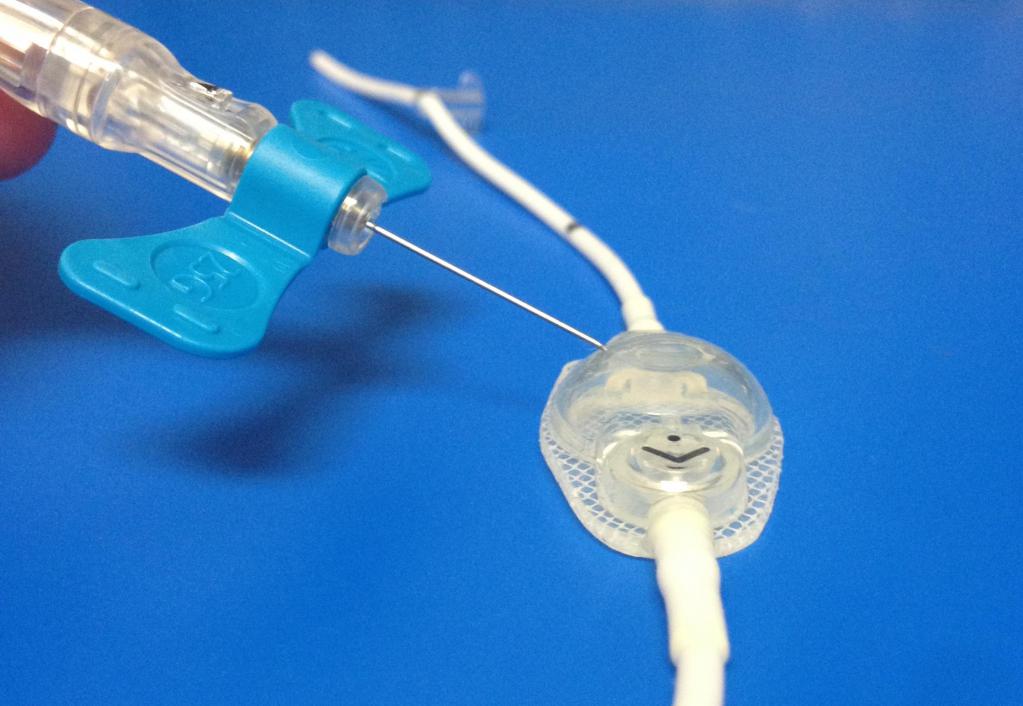

Вентрикуло-перитонеальный шунт: Показания и применение

Раздел: Фотоальбом решений